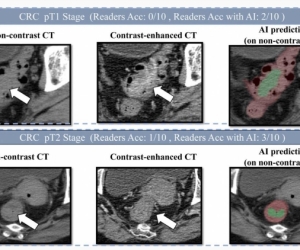

阿里巴巴发布创新癌症AI模型 助力肠癌筛